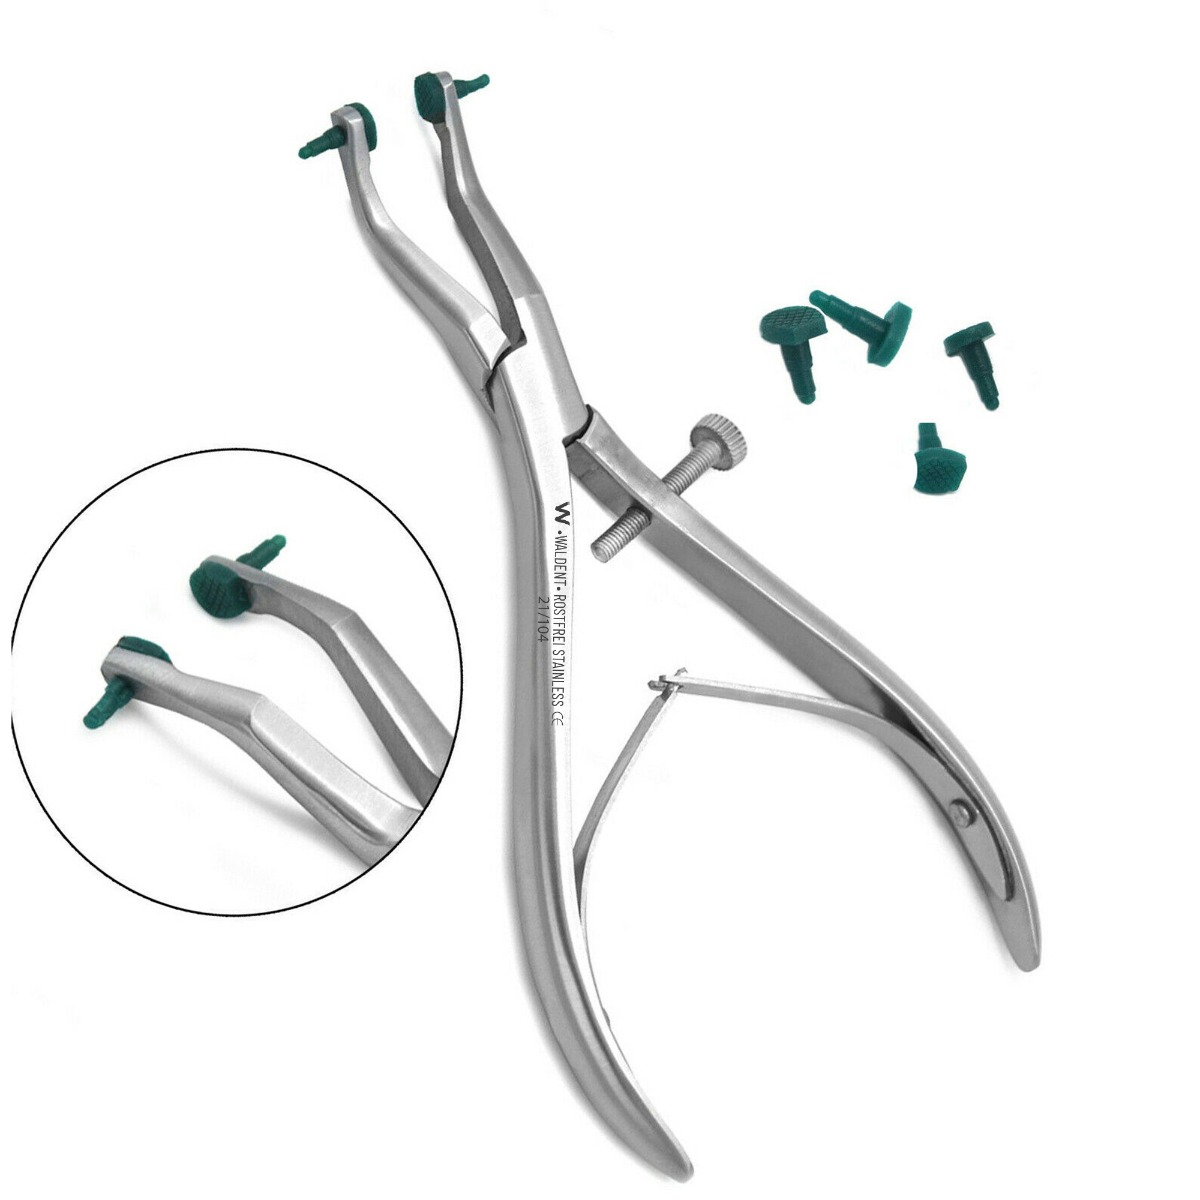

- Manual Crown Removal: Manual techniques involve using crown removing pliers, which provide a strong grip on the crown for gentle extraction. These pliers are designed with specialized tips to grasp the crown securely without causing damage.

A: Utilize specialized crown removing pliers with precise grip mechanisms to minimize stress on fragile teeth. Incorporate micro-movement techniques to gradually dislodge the crown, reducing the risk of fractures.

A: Prioritize tissue management and isolation to access subgingival margins. Utilize specialized pliers or cutting burs with fine tips for precise removal, minimizing tissue trauma while ensuring effective crown detachment.